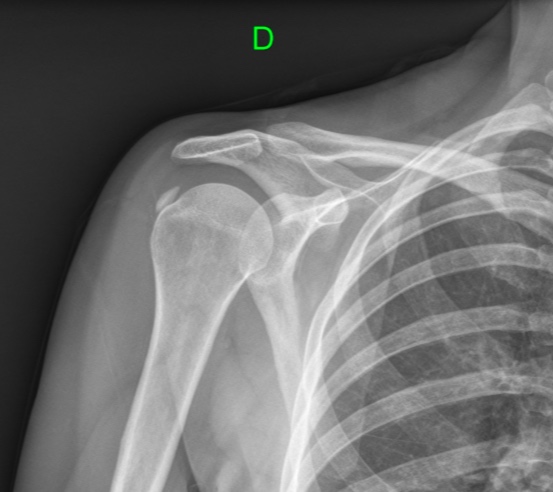

Mujer de 42 años, peluquera de profesión, que refiere omalgia al elevar el brazo. Tras una semana de evolución el dolor se presenta también en reposo y por las noches. ¿Cuál es el diagnóstico más probable según la radiografía del hombro?:

- Capsulitis adhesiva.

- Lesión del labrum

- Bursitis subacromial.

- Tendinitis cálcica.

Respuesta correcta: 4